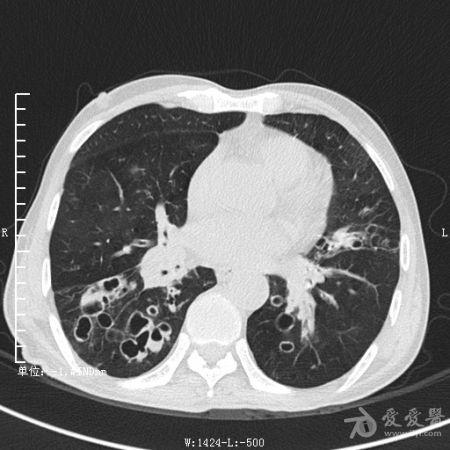

典型支气管扩张及肺水肿CT片

典型支气管扩张肺水肿